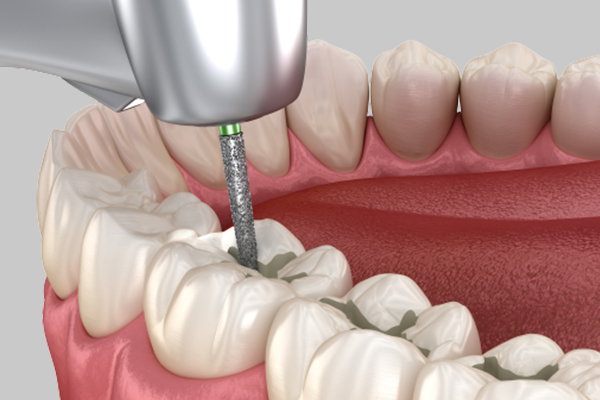

• Pulpitis

Inflammation has progressed to the dental pulp, causing severe pain that may become difficult to tolerate.

Root Canal Treatment + Crown